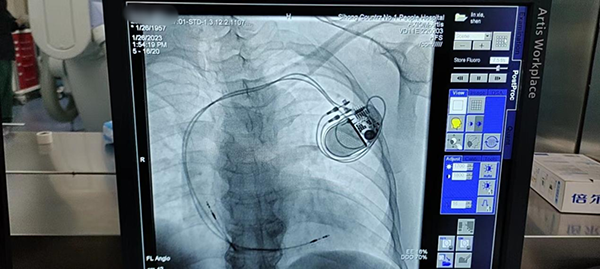

黃淮網(wǎng) 近日,徐醫(yī)附院泗洪分院心內(nèi)科成功開展首例永久性心臟起搏器植入術(shù),實(shí)現(xiàn)了在該診療技術(shù)上“零”的突破。

近期癥狀又有所加重,于是她來到徐州醫(yī)科大學(xué)附屬醫(yī)院泗洪分院就診,心內(nèi)科接診后,診斷為病態(tài)竇房結(jié)綜合征,行動(dòng)態(tài)心電圖提示:平均心率42次/MIN,最大RR間歇3.6s,此時(shí)患者已有具備“心臟永久起搏器”植入指征,如果不及時(shí)救治,心臟隨時(shí)可能停跳,危及生命。

隨后,心內(nèi)科副主任醫(yī)師許超國與患者及家屬積極溝通,建議盡快植入心臟永久起搏器以改善臨床癥狀、減少致死風(fēng)險(xiǎn);颊呓(jīng)過慎重考慮后,決定進(jìn)行手術(shù)。為保證患者安全、手術(shù)順利進(jìn)行,許超國立即與徐醫(yī)附院專家李承宗主任聯(lián)系,就手術(shù)相關(guān)事項(xiàng)進(jìn)行了仔細(xì)分析和研究,制定了詳細(xì)周密的手術(shù)方案。

由于患者病情緊急,1月26日(大年初五),李承宗主任放棄春節(jié)假期趕到泗洪,在他指導(dǎo)下,醫(yī)護(hù)團(tuán)隊(duì)默契配合、細(xì)致操作,僅用時(shí)90分鐘,就成功實(shí)施心臟永久起搏器植入手術(shù)。沈阿姨術(shù)后高興地說:“我這胸悶的感覺沒有了,心臟跳得也有勁了”。她兒子表示十分感謝:“再也不用奔走異地求醫(yī),在家門口就有一流的專家,可以享受到一流的醫(yī)療技術(shù),我們年后也可以放心地出去打工了”。

這是泗洪縣第一人民醫(yī)院的首臺(tái)永久起搏器植入術(shù),填補(bǔ)了醫(yī)院的技術(shù)空白。去年在李承宗主任的幫扶下,科室先后開展了室上性心動(dòng)過速、心房顫動(dòng)的射頻消融術(shù),真正實(shí)現(xiàn)技術(shù)下沉,補(bǔ)齊縣醫(yī)院醫(yī)療服務(wù)短板,標(biāo)志著縣級(jí)醫(yī)院在心臟起搏與電生理專業(yè)的全覆蓋。